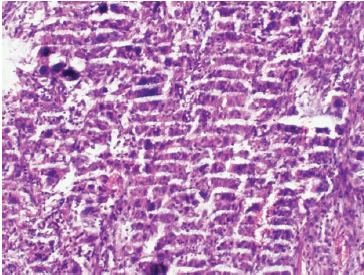

七、切片染色效果不佳

切片染色效果不佳可能是由于染色時間過長或過短、染色液濃度不合適等原因造成的。

為了改善染色效果,我們可以按照以下步驟進行調(diào)整:

①根據(jù)實驗需要,選擇合適的染色液種類和濃度。

②控制染色時間,確保染色充分且不過度。